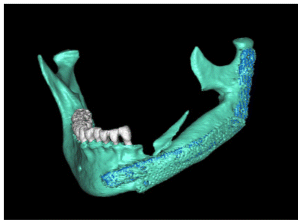

The patient after surgery continued under observation and could not continue with her treatment due to the Covid epidemic, resuming the treatment on 03/02/2014 for the reassessment by CT the new bone formed in the area of surgery was observed by two programs Blues Sky Bio and Mimics of Materialise the values in Hounsfield units were determined in each of the CT slices at the sites planned for the placement of three implants, the values ranged from 209 U. Hounsfield to 1372 U. Hounsfield (Figs, 15,16,17,18).

In the CT scan, the bone regeneration of the morphogenetic protein BMP2 (Cowell PLUS BMP) and the growth factors with the Chucron technique were verified, managing to observe a good bone conformation, however, a bone formation was observed towards the upper part of the jaw that did not follow any anatomical pattern of the mandibular body and was attached to the mandibular body. (Figures 19,20, 21)